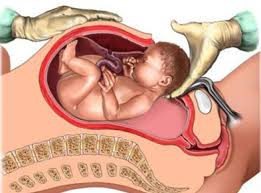

Caesarean Section (C-Section)

A Caesarean Section is a surgical procedure used to deliver a baby through incisions made in the mother's abdomen and uterus. This method is often necessary in cases where a vaginal delivery poses a risk to the mother or baby, such as in cases of fetal distress, abnormal positioning, or medical complications.